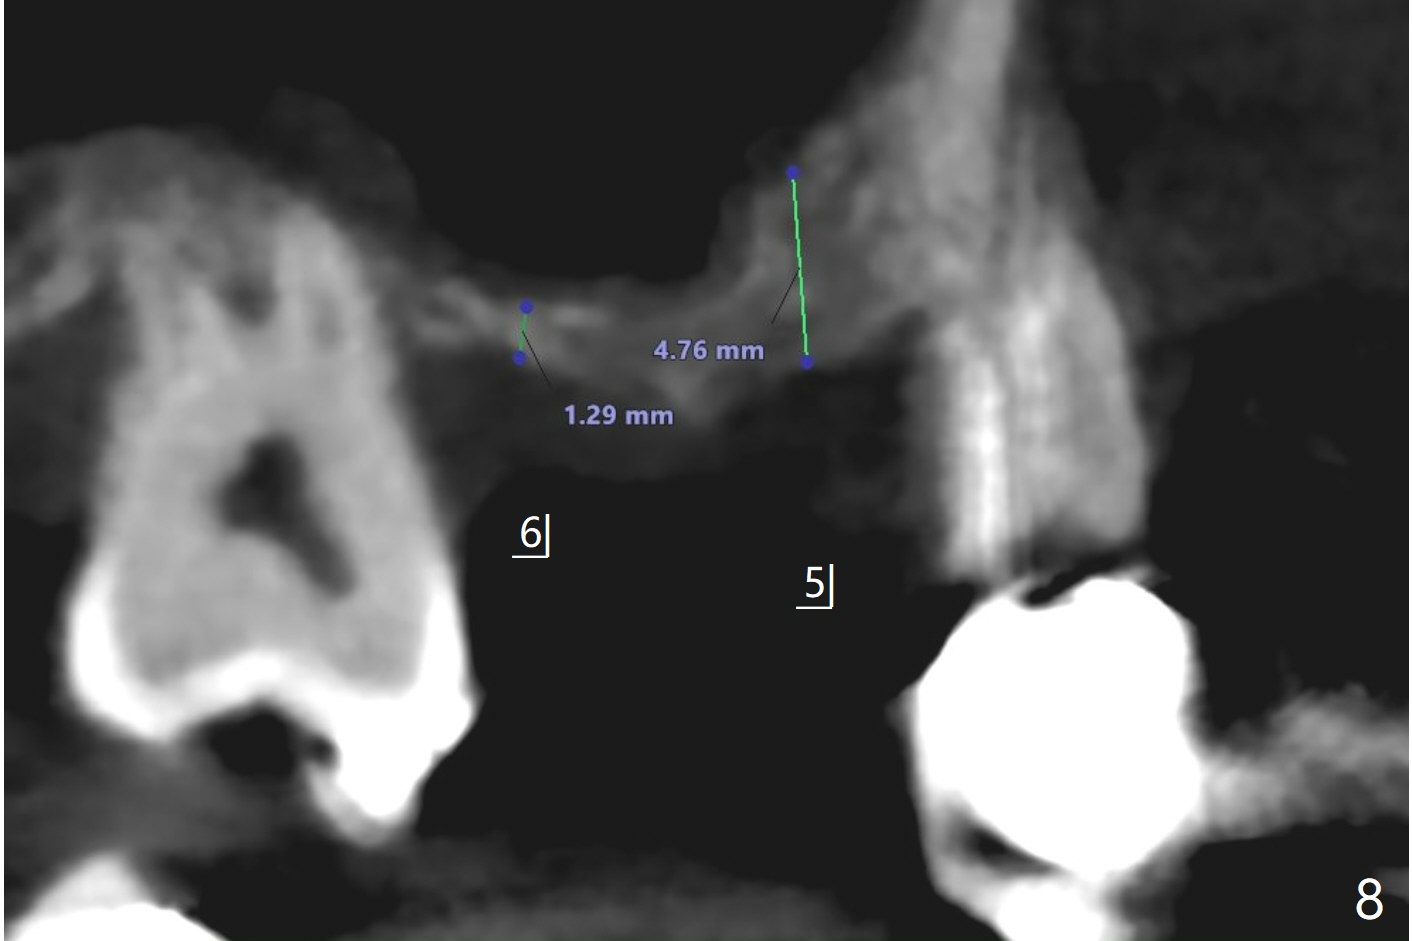

49岁女(图一)同意先做右上5,6种植(图二,三),但是必须先做外提升,高至5根尖(图二:红线),范围延申至右上7,后者骨质吸收厉害(图三:*),预后不佳。后者可能是好几年的事情,是杞人忧天?准备DIO Sinus Master Kit, sinus curettes (curved), a round flat osteotome (in sinus box) and mallet as well as PRFx2。图三黄线代表外提升入口。外提失败因为遇到动脉(图四),上牙槽中血管穿过上颌窦前壁(图五)。实验室建议在右上5种植(图六至八)。结果内提同期种植。